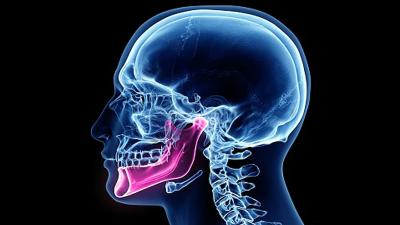

मानवी शरीराचा एक नवीन अवयव संशोधनात समोर आला आहे. याआधी कधीही स्टडीमध्ये त्याचा खुलासा झाला नाही. हा अवयव आपल्या खालच्या जबड्याच्या शेवटी स्थित असतो. ज्याच्या मदतीने आपला जबडा हलतो. हा गालाच्या आत असलेल्या स्नायूंचा खोल थर आहे. त्याच्यामुळे जबड्याने वरखाली करण्यास मदत मिळते.

या तपासात गालातील स्नायूंमध्ये आणखी एक खोल थर आहे, जो रचनेच्या आधारावर इतर दोन स्तरांपेक्षा वेगळा आहे. हा स्नायू प्रत्यक्षात हाडासारखा दिसतो. हा नवीन स्नायू हाडासारखा दिसण्याचे कारण म्हणजे त्याच्या आजूबाजूला हाडे असतात. ज्यांना गालाची हाडे(Cheek Bones) म्हणतात.

हा कानाजवळ समोरच्या बाजूला स्थित आहे. शास्त्रज्ञांनी खालच्या जबड्याच्या अगदी वर त्रिकोणी आकाराचा फुगवटा देखील पाहिला, जो या नवीन स्नायूमुळे तयार झाला होता. जे या नवीन स्नायूमुळे तयार झाले आहे. हा स्नायू जबड्याला उघडझाप करण्यासाठी, हालचालींसाठी मदत करतो.

या नवीन अवयवाला मस्क्यूलस मैसेटर पार्स कोरोनिडिया (Musculus Masseter Pars Coronidea) असं नाव देण्यात आलं आहे. सामान्य भाषेत मासेटरचा कोरोनॉइड भाग. हा शोध यासाठी देखील महत्त्वाचा आहे कारण डॉक्टर आणि शास्त्रज्ञ आता जबड्याच्या स्नायूंचा अधिक अभ्यास करू शकतील.